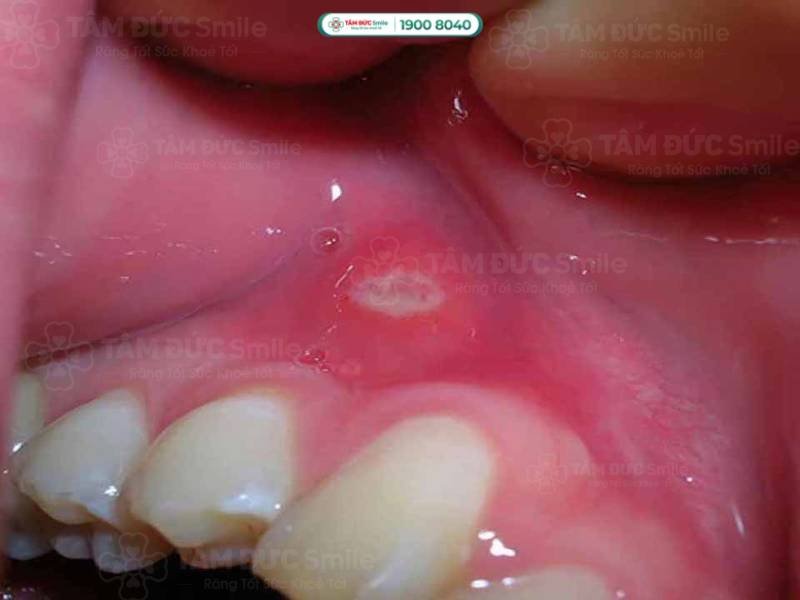

Nướu răng bị sưng do nhiệt miệng là tình trạng phổ biến và gây nhiều khó chịu. Nhiệt miệng xuất hiện dưới dạng các vết loét nhỏ, trắng hoặc vàng trong miệng và nướu. Nhiệt miệng lan rộng và bị viêm nhiễm có thể gây sưng nướu.

Vết nhiệt miệng nếu không tự khỏi, khi trở thành viêm cấp thường bị tấy đỏ và đau rát. Thậm chí, người bị nhiệt nặng còn sốt cao, nổi hạch ở góc hàm khiến việc ăn uống trở nên khó khăn.

Nướu răng bị sưng do nhiệt miệng